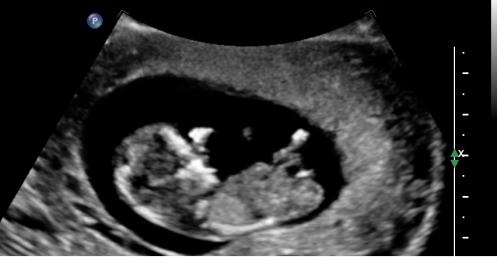

Attachment 7497Attachment 7498Attachment 7499

Hmmmm Im going to say boy but its just a guess. It is flat though so could totally go the other way - Good Luck :)

i'm slightly leaning boy on this one.

thank you for the quick response.. just curious is it pic one that makes you lean boy??

pic 3 made me lean boy.